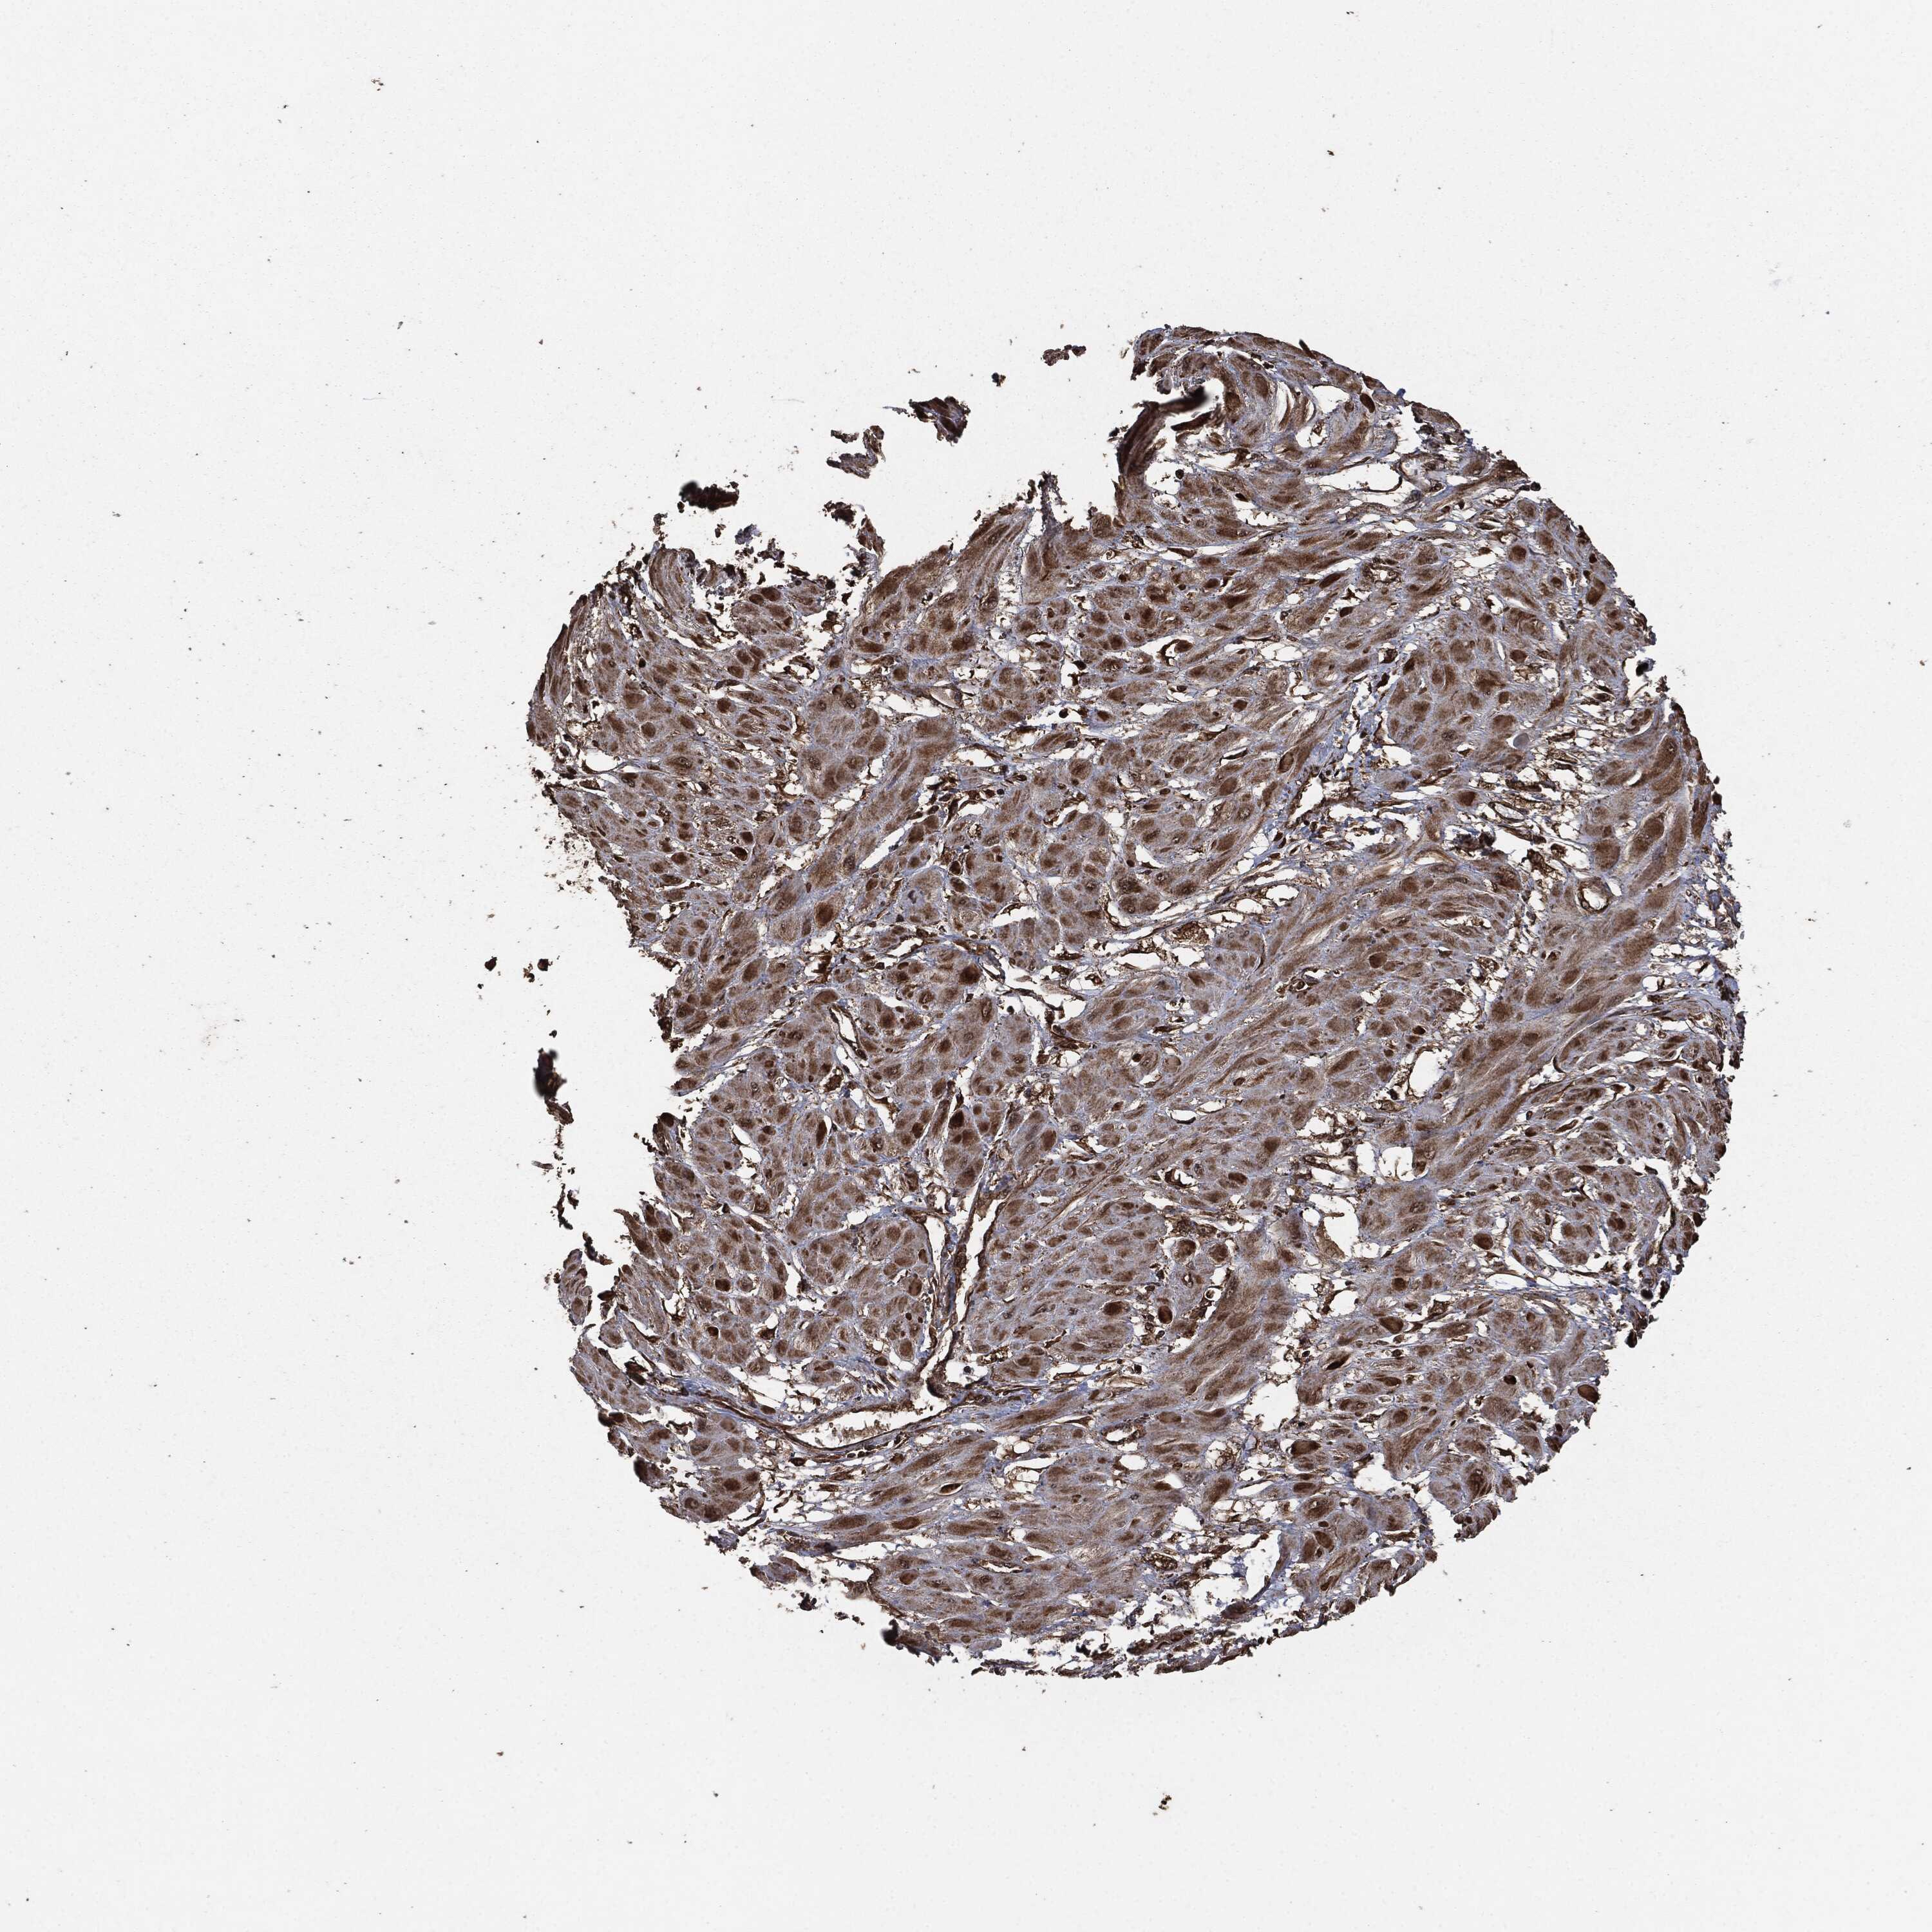

CERVICAL CANCER - Protein expressioni

A mouse-over function shows sample information and annotation data. Click on an image to view it in a full screen mode. Samples can be filtered based on level of antibody staining by selecting one or several of the following categories: high, medium, low and not detected. The assay and annotation is described here.

Note that samples used for immunohistochemistry by the Human Protein Atlas do not correspond to samples in the TCGA dataset.

Antibody stainingi

Antibody staining in the annotated cell types in the current human tissue is reported as not detected, low, medium, or high, based on conventional immunohistochemistry profiling in selected tissues. This score is based on the combination of the staining intensity and fraction of stained cells.

Each image is clickable and will lead to virtual microscopy that enables deeper exploration of all samples and also displays staining intensity scores, fraction scores and subcellular localization as well as patient and tissue information for each sample.

Staining

High

Medium

Low

Not detected

Intensity

Strong

Moderate

Weak

Negative

Quantity

>75%

75%-25%

<25%

None

Location

Nuclear

Cytoplasmic/membranous

Cytoplasmic/membranous,nuclear

Adenocarcinoma, NOS

Squamous cell carcinoma, NOS